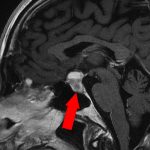

360

'22年12月

70代

右前頭葉膠芽腫

頭蓋内腫瘍摘出術

No.’22_117 手術前1

No.’22_117 手術前2